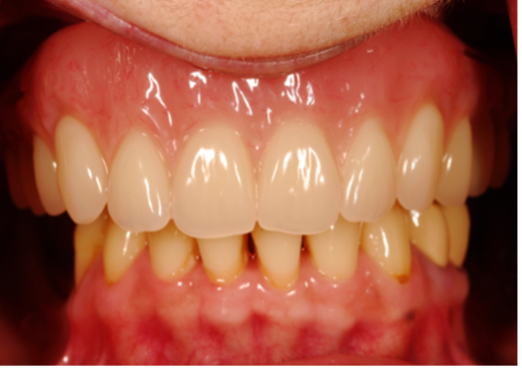

(9.) Branemark “High water” design.

Figure 9

(10.) Branemark “High water” design.

Figure 10

Many factors should be considered when designing implant-supported restorations to reduce the risk of peri-implantitis affecting physical removal of bacterial plaque at the FMG. Included are oral hygiene devices, accessibility, prosthetic shapes, and patient ability to comply with oral hygiene procedures. The design should be conveniently hygienic so patients can easily comply with the recommended oral hygiene procedures. Physical removal of bacterial plaque on the intaglio surface at and above the FMG reduces the risk of peri-implantitis in the sub-gingival transmucosal tissue around dental implants. The original fixed prosthetic design presented by Branemark, a "High water design", provided access to all surfaces for oral hygiene management without a patient complaint of food accumulation (Figure 9 and Figure 10). Notably, relief above the gingiva was not patient complaint with this design. Lack of embrasure access to the FMG and intaglio surfaces for oral hygiene management can lead to peri-implantitis (Figure 11 and Figure 12). Stein recommended a convex modified ridgelap pontic design with lingual and palatal access to facilitate plaque removal from the intaglio surface under pontics in fixed prosthetics with dental floss.20 These shapes should be standard for fixed implant-supported restorations whether individual or multi-unit restorations made of ceramo-metal or milled zirconia (Figure 13 through Figure 16).